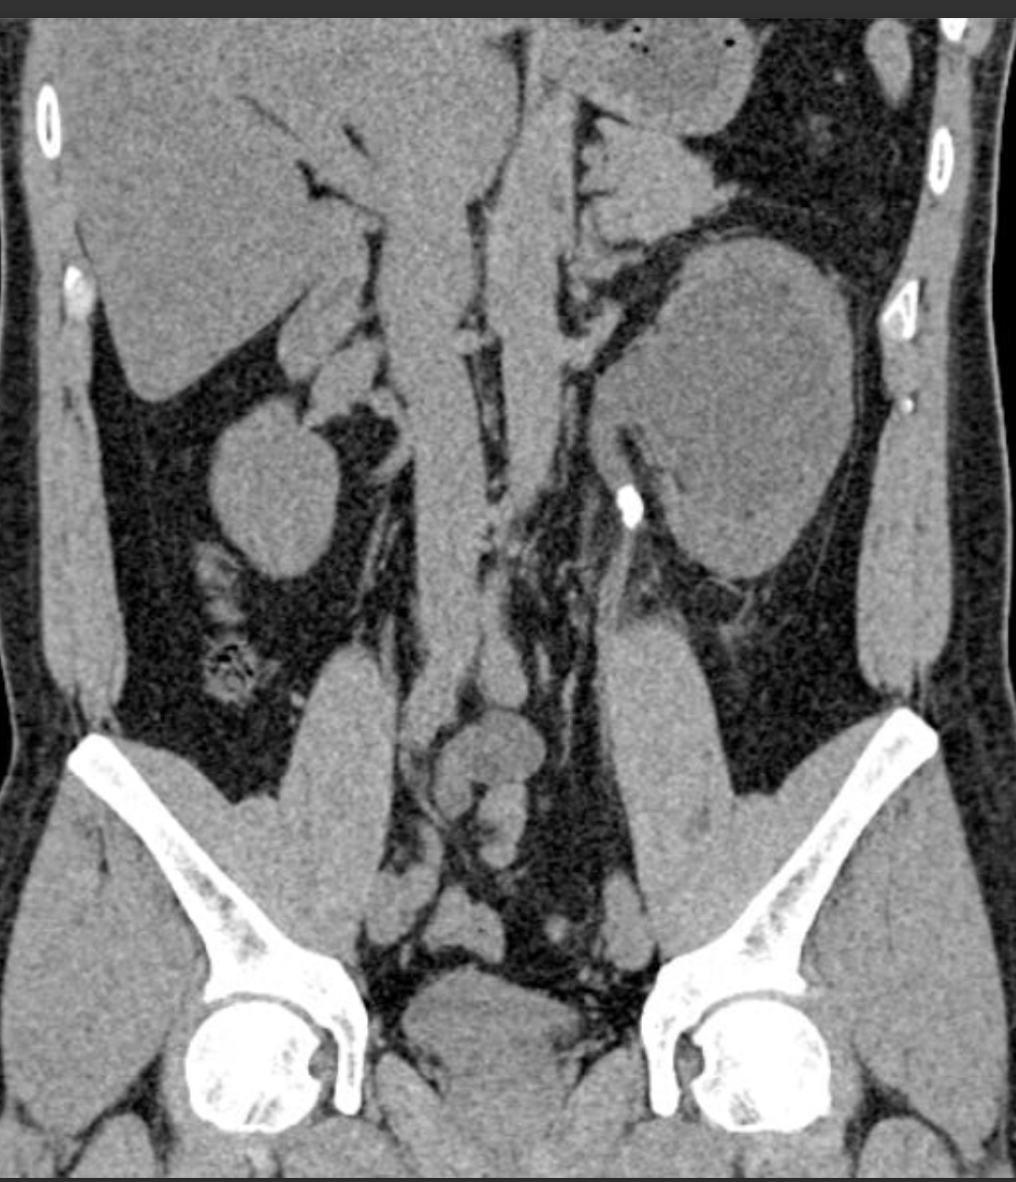

Non Contrast CT scan

Can see exactly where it’s blocked and other organs involved

Can also see if there’s hydronephrosis (swelling of the kidney due to back pressure)

You can also see peinephric fat stranding